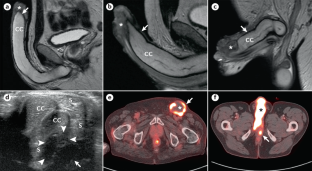

Kayes, O. et al. The role of magnetic resonance imaging in the local staging of penile cancer. Eur. Urol. 51, 1313–1318 (2007).

Petralia, G. et al. Local staging of penile cancer using magnetic resonance imaging with pharmacologically induced penile erection. Radiol. Med. 113, 517–528 (2008).

Rosevear, H. M. et al. Utility of ¹-F-FDG PET/CT in identifying penile squamous cell carcinoma metastatic lymph nodes. Urol. Oncol. 30, 723–726 (2012).

The authors affirm that human research participants provided informed consent for publication of the images in Figure 3 and Figure 6.